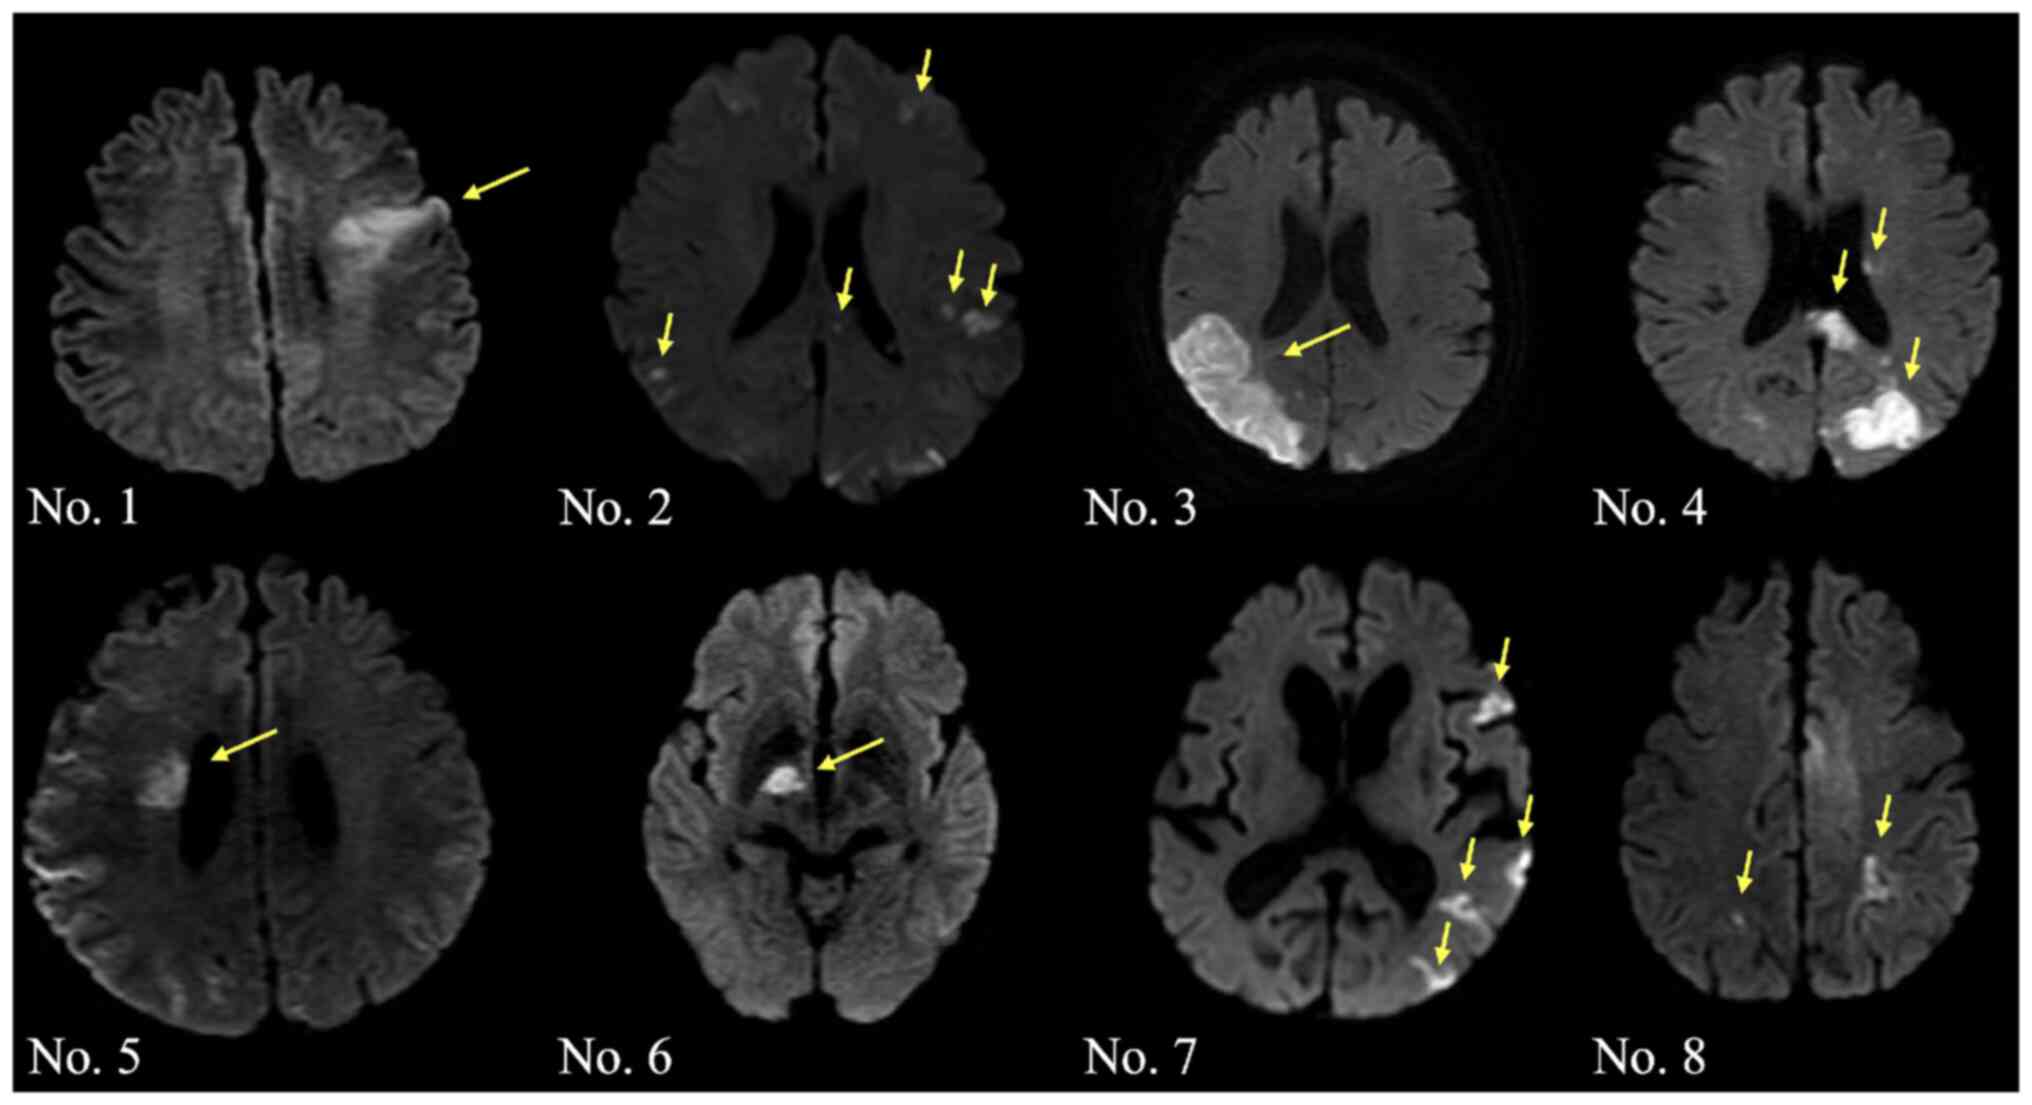

The cerebral infarction lesions detected by MRI of the brain (diffusion-weighted image) were as follows: Single lesion in one vascular territory infarction in 4 cases (cases 1, 3, 5 and 6) and multiple infarctions in 4 cases (cases 2, 4, 7 and 8) (Fig. 1). Neurological symptoms at onset were as follows: Disorientation in 5 cases, hemiparesis in 3 cases, dysarthria in 3 cases and loss of consciousness in 1 case.

Figure 1.

Diffusion-weighted image for each patient. Cases 1, 3, 5 and 6 showed a single lesion of cerebral fraction, while cases 2, 4, 7 and 8 showed multiple lesions of cerebral fraction. Arrows represent the infarction lesions.

It has been reported that infarcts involving multiple vascular areas detected by diffusion-weighted imaging are highly sensitive to Trousseau syndrome-related cerebral infarction (18). A previous study that assessed the radiological features of 31 patients with Trousseau syndrome-related cerebral infarction showed that multiple lesions in multiple vascular territories were the most frequent pattern (87.1%; 27/31) (36). By contrast, only 50% of the patients in the present study exhibited this feature. Due to the small number of cases, further research on patterns of cerebral infarction in patients with GI cancer in a large number of patients is needed.